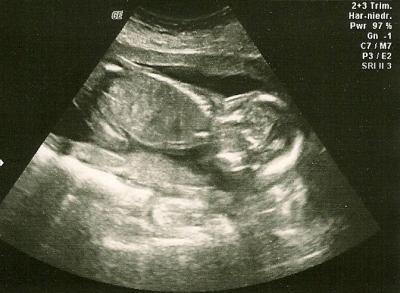

Hallo zusammen, ich hatte heute (SSW 18+5) den zweiten großen Ultraschall. Zum Glück ist alles ok, bin mal wieder sehr erleichtert. Am 26.11. haben wir dann das Organscreening in der Pränatalprasix. Das Mädchen-Outing wurde übrigens nochmal bestätigt. Seit zwei Tagen ist allerdings, nach vier Wochen Ruhe, meine Übelkeit wieder zurück. Das beunruhigt mich im Moment irgendwie ein bisschen. Ich hoffe, das erledigt sich schnell wieder von selbst. Ach, ich bin seit der Fehlgeburt halt sehr schnell verunsichert. Ist die Übelkeit bei euch auch wieder gekommen oder habt ihr Ruhe? LG

Bild zu FA-Bericht + Übelkeit wieder da - Forum für April - Mamis

Schön zu lesen dass alles gut ist! Das Bild ist auch voll süss!!! Bei mir ist die Übelkeit noch gar nicht weg. Es ist zwar viel besser, abef ich übergebe mich immer noch öfters. Immerhin seit 2 Wochen nicht mehr täglich. Ich hoffe es geht bald ganz vorbei, auch bei dir.